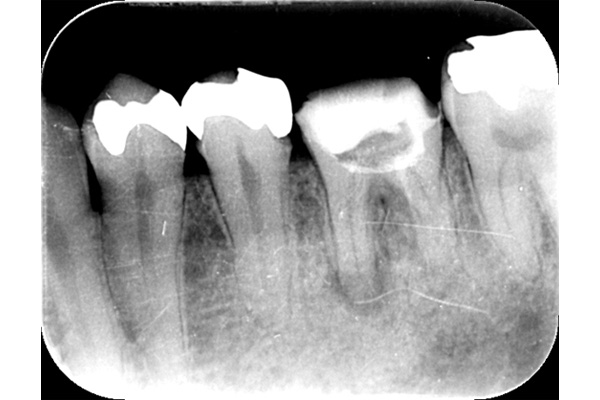

こちらは根の治療の経験がある歯ではありませんが、歯茎が大きく腫れていらした患者様です。レントゲンを撮ってみると原因となっていそうな、2本怪しい歯がありました。過去の虫歯の経緯から後ろの歯の方が怪しいと判断し、1本だけ治療を行いました。

治療後、腫れの大きさの確認のためにCTを撮影すると、上顎洞にまでおよぶ大きな炎症があり、骨が大きくなくなっていることが確認できました。

基礎に忠実に根の中をしっかり清掃し、防腐剤を詰めて経過をみるために3ヶ月後に再度CTを撮影しました。以前とは比べ物にならないくらい、上顎洞の炎症はなくなり。上顎洞を隔てる骨の再生もできました。 またこの治療で一番良かったのは、治療しなければならない歯とそうでない歯を鑑別できたことです。手前の歯はやはり治療する必要がなかったのです。

初診終了後にCT撮影です。上顎洞と歯が連続してしまうくらい炎症が広がっています。

根の先に黒い影があり、2本ともあやしいです。

きっちり清掃を行い防腐剤をつめました。

まだ根の先端に黒い影はあるが、治癒傾向にあると判断できます。